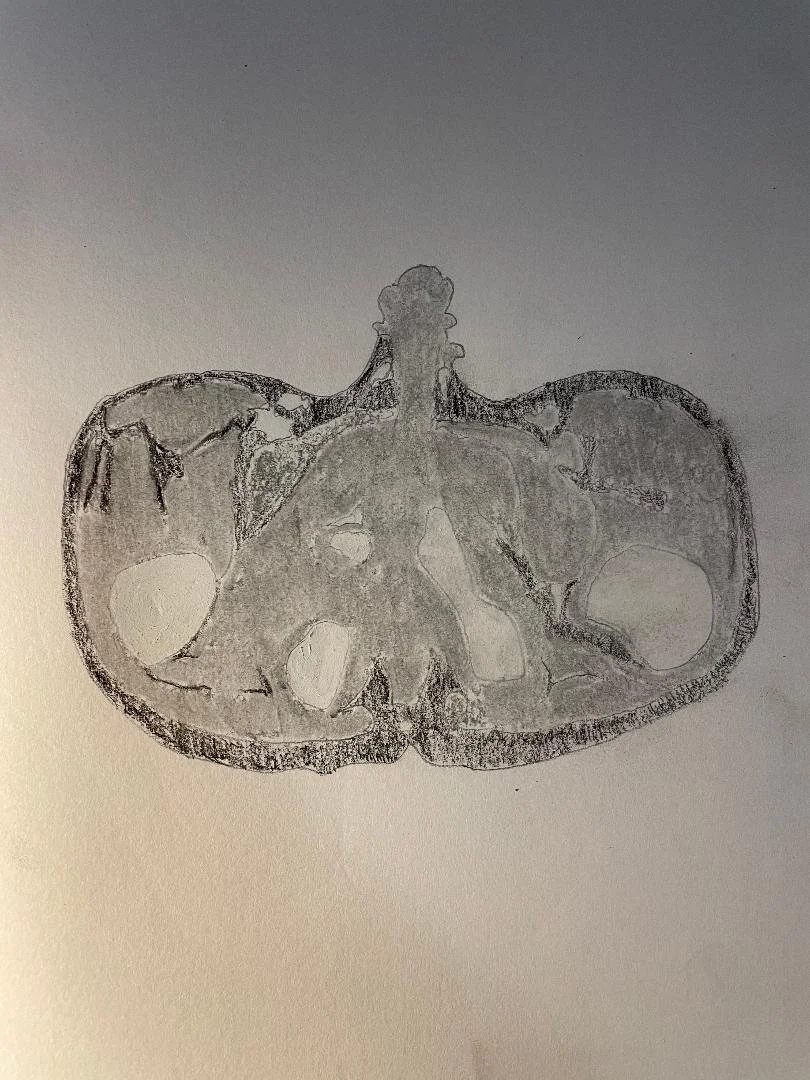

Osteomyelitis of the ischiopubic synchondrosis

Tuberous sclerosis

Subacute infarct

Toxic/inhalational leukoencephalopathy